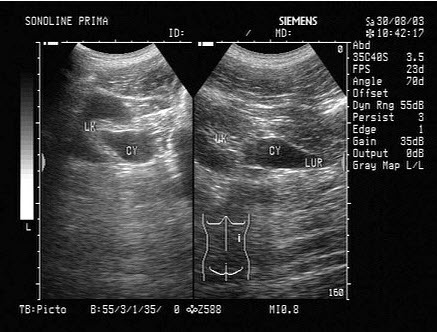

某患者脾脏声像图表现如图,诊断为()

A.正常脾脏

B.脾大

C.脾破裂

D.脾梗死

E.以上都不是